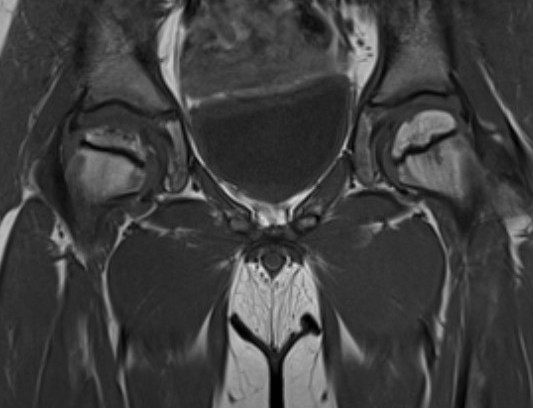

MRI

Advantage

- can assess amount of cartilaginous head outside of acetabulum

- very good way of assessing containment of cartilage head

Stuhlberg

Based on congruency & sphericity